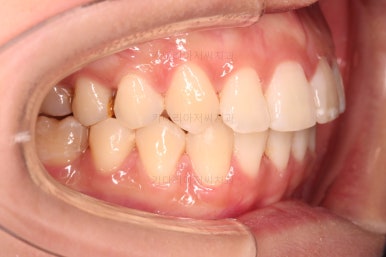

전후 비교 해볼게요.

입안의 모습은 더할나위 없이 잘 개선되었고요.

상하좌우 이 뽑은 위치와 크기가 달라 이정도 중앙선은 매우 잘 맞는 상황인거고요.

얼굴모습도 옆라인이 매우 좋아졌죠.

입이 들어가고 턱선이 살아나게끔 해드렸어요.

임플란트도 안해도 되면서 사랑니까지 잘 사용하고 2년 반 밖에 치료기간도 안걸린 매우 좋은 치료였다고 생각되어집니다.

이상 어금니가 결손되어 있고, 돌출입이었던 환자분을 미니스크류를 이용해 사랑니까지 당겨와서 임플란트 없이 치료를 한 부산사랑니교정 치료사례였습니다.